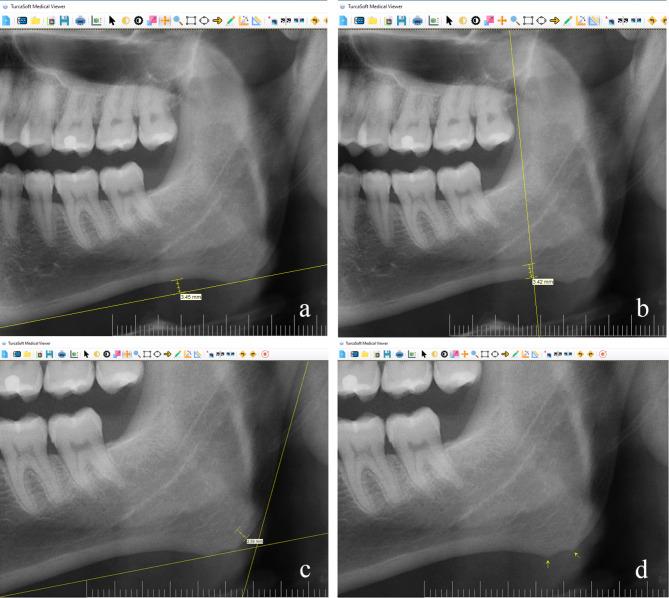

This is the first study to report both cortical and trabecular bone evaluation of mandibles in bruxers, within the knowledge of the authors. The purpose of this study was to evaluate the effects of bruxism on both the cortical and the trabecular bone in antegonial and gonial regions of the mandible, which is the attachment of the masticatory muscles, by using panoramic radiographic images.

In this study, the data of 65 bruxer (31 female, 34 male) and 71 non-bruxer (37 female, 34 male) young adult patients (20-30 years) were evaluated. Antegonial Notch Depth (AND), Antegonial-Index (AI), Gonial-Index, Fractal Dimension (FD) and Bone Peaks (BP) were evaluated on panoramic radiographic images. The effects of the bruxism, gender and side factors were investigated according to these findings. The statistical significance level was set atP ≤ 0.05.

The mean AND of bruxers (2.03 ± 0.91) was significantly higher than non-bruxers (1.57 ± 0.71; P < 0.001). The mean AND of males was significantly higher than females on both sides (P < 0.05). The mean AI of bruxers (2.95 ± 0.50) was significantly higher than non-bruxers (2.77 ± 0.43; P = 0.019). The mean FD on each side was significantly lower in bruxers than in non-bruxers (P < 0.05). The mean FD of males (1.39 ± 0.06) was significantly higher than females (1.37 ± 0.06; P = 0.049). BP were observed in 72.5% of bruxers and 27.5% of non-bruxers. The probability of existing BP, in bruxers was approximately 3.4 times higher than in non-bruxers (P = 0.003), in males was approximately 5.5 times higher than in females (P < 0.001).

According to the findings of this study, the morphological differences seen in cortical and trabecular bone in the antegonial and gonial regions of the mandible in bruxers can be emphasized as deeper AND, higher AI, increased of existing BPs, and lower FD, respectively. The appearance of these morphological changes on radiographs may be useful for indication and follow-up of bruxism. Gender is an effective factor on AND, existing BP and FD.